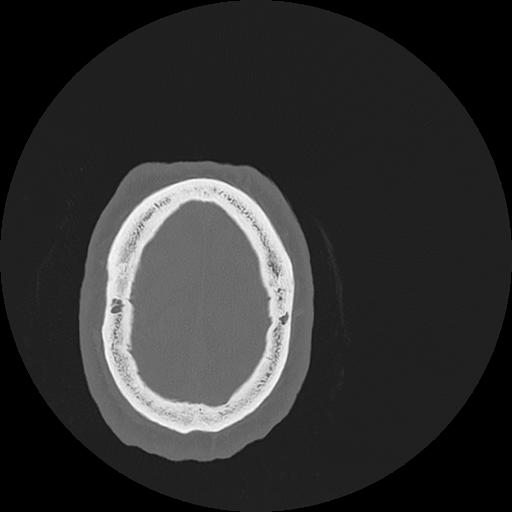

7 HUESO,,Vol,0.5,HUESO,,